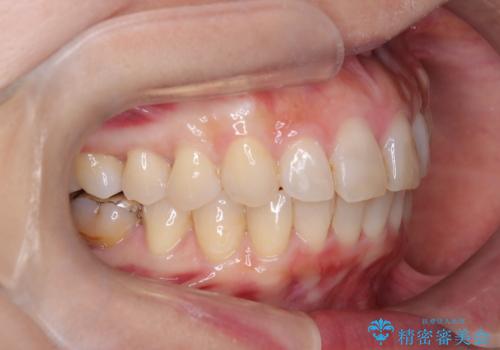

【インビザライン】前歯の凸凹を治したい

- 前歯の凸凹を主訴に来院されました。

臼歯部の遠心移動を行いながらスペースを作り、インビザラインにて前歯をきれいに並べることができました。

今回の治療計画では臼歯部の遠心移動とIPRを行っています。